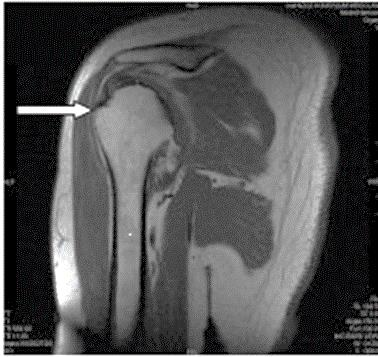

Którą strukturę anatomiczną oznaczono na obrazie rezonansu magnetycznego?

A. Trzon kości ramiennej.

B. Głowę kości ramiennej.

C. Guzek większy kości ramiennej.

D. Guzek mniejszy kości ramiennej.